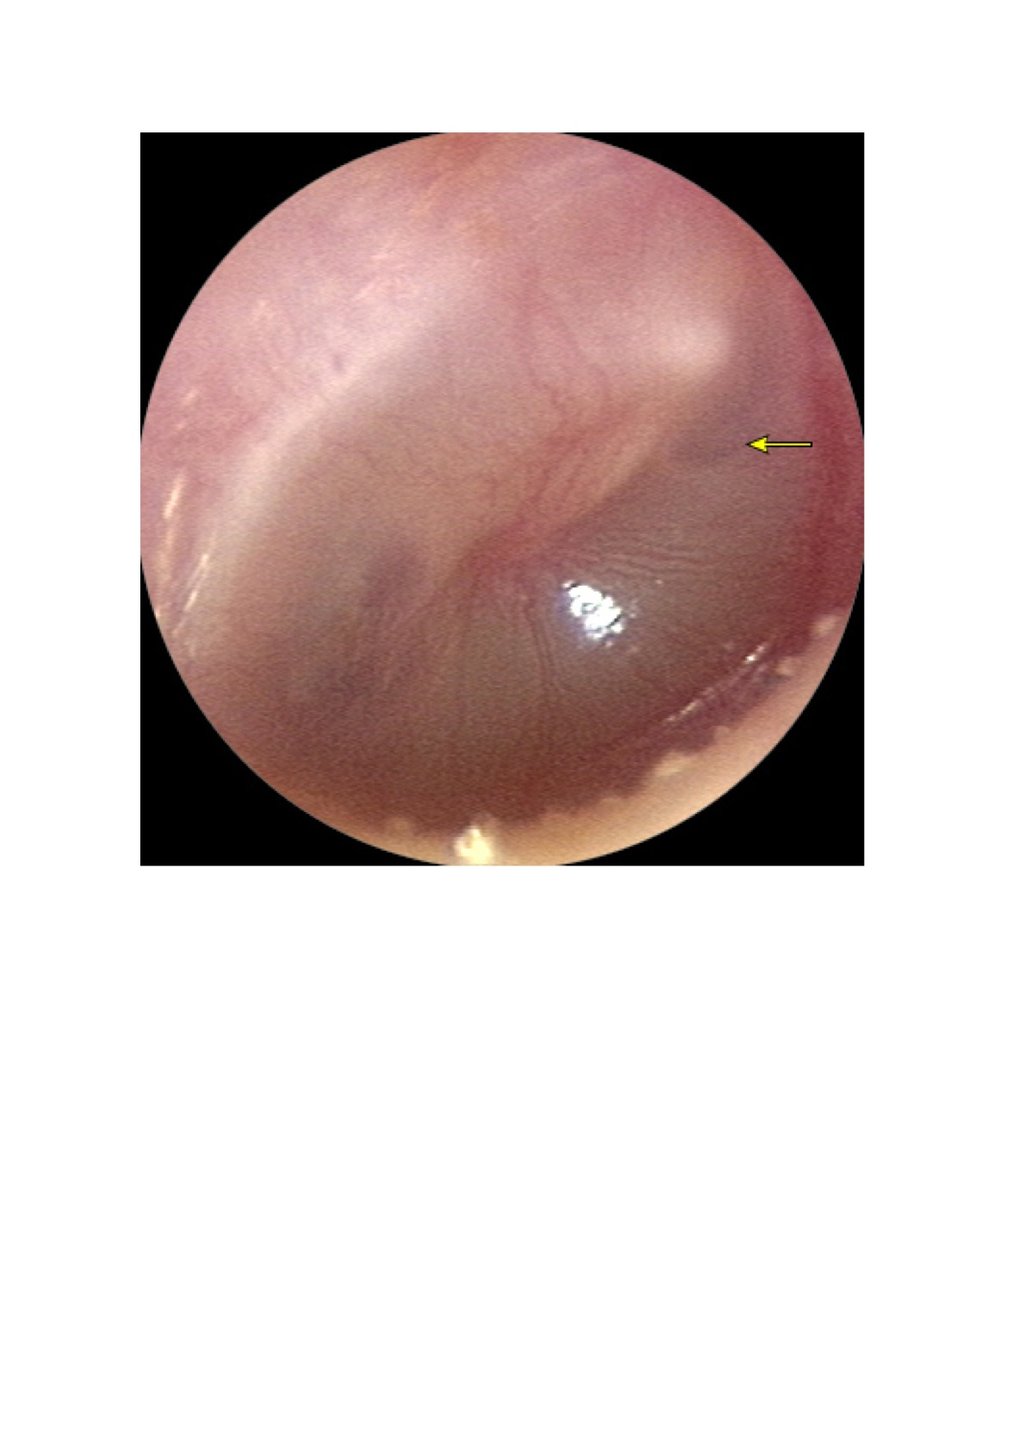

• segni obiettivi di infiammazione della membrana timpanica (iperemia marcata, estroflessione),

• presenza di essudato endotimpanico (MT sporgente o otorrea da perforazione spontanea).

La sola iperemia della MT, la perdita del triangolo luminoso o la retrazione timpanica

non sono sufficienti per la diagnosi e indicano più probabilmente un’otite media effusiva (OME).

A. Otite media acuta precoce con infiammazione.

B. Versamento purulento con livello di aria e liquido.

C. Versamento purulento sporgente che riempie l'orecchio medio.